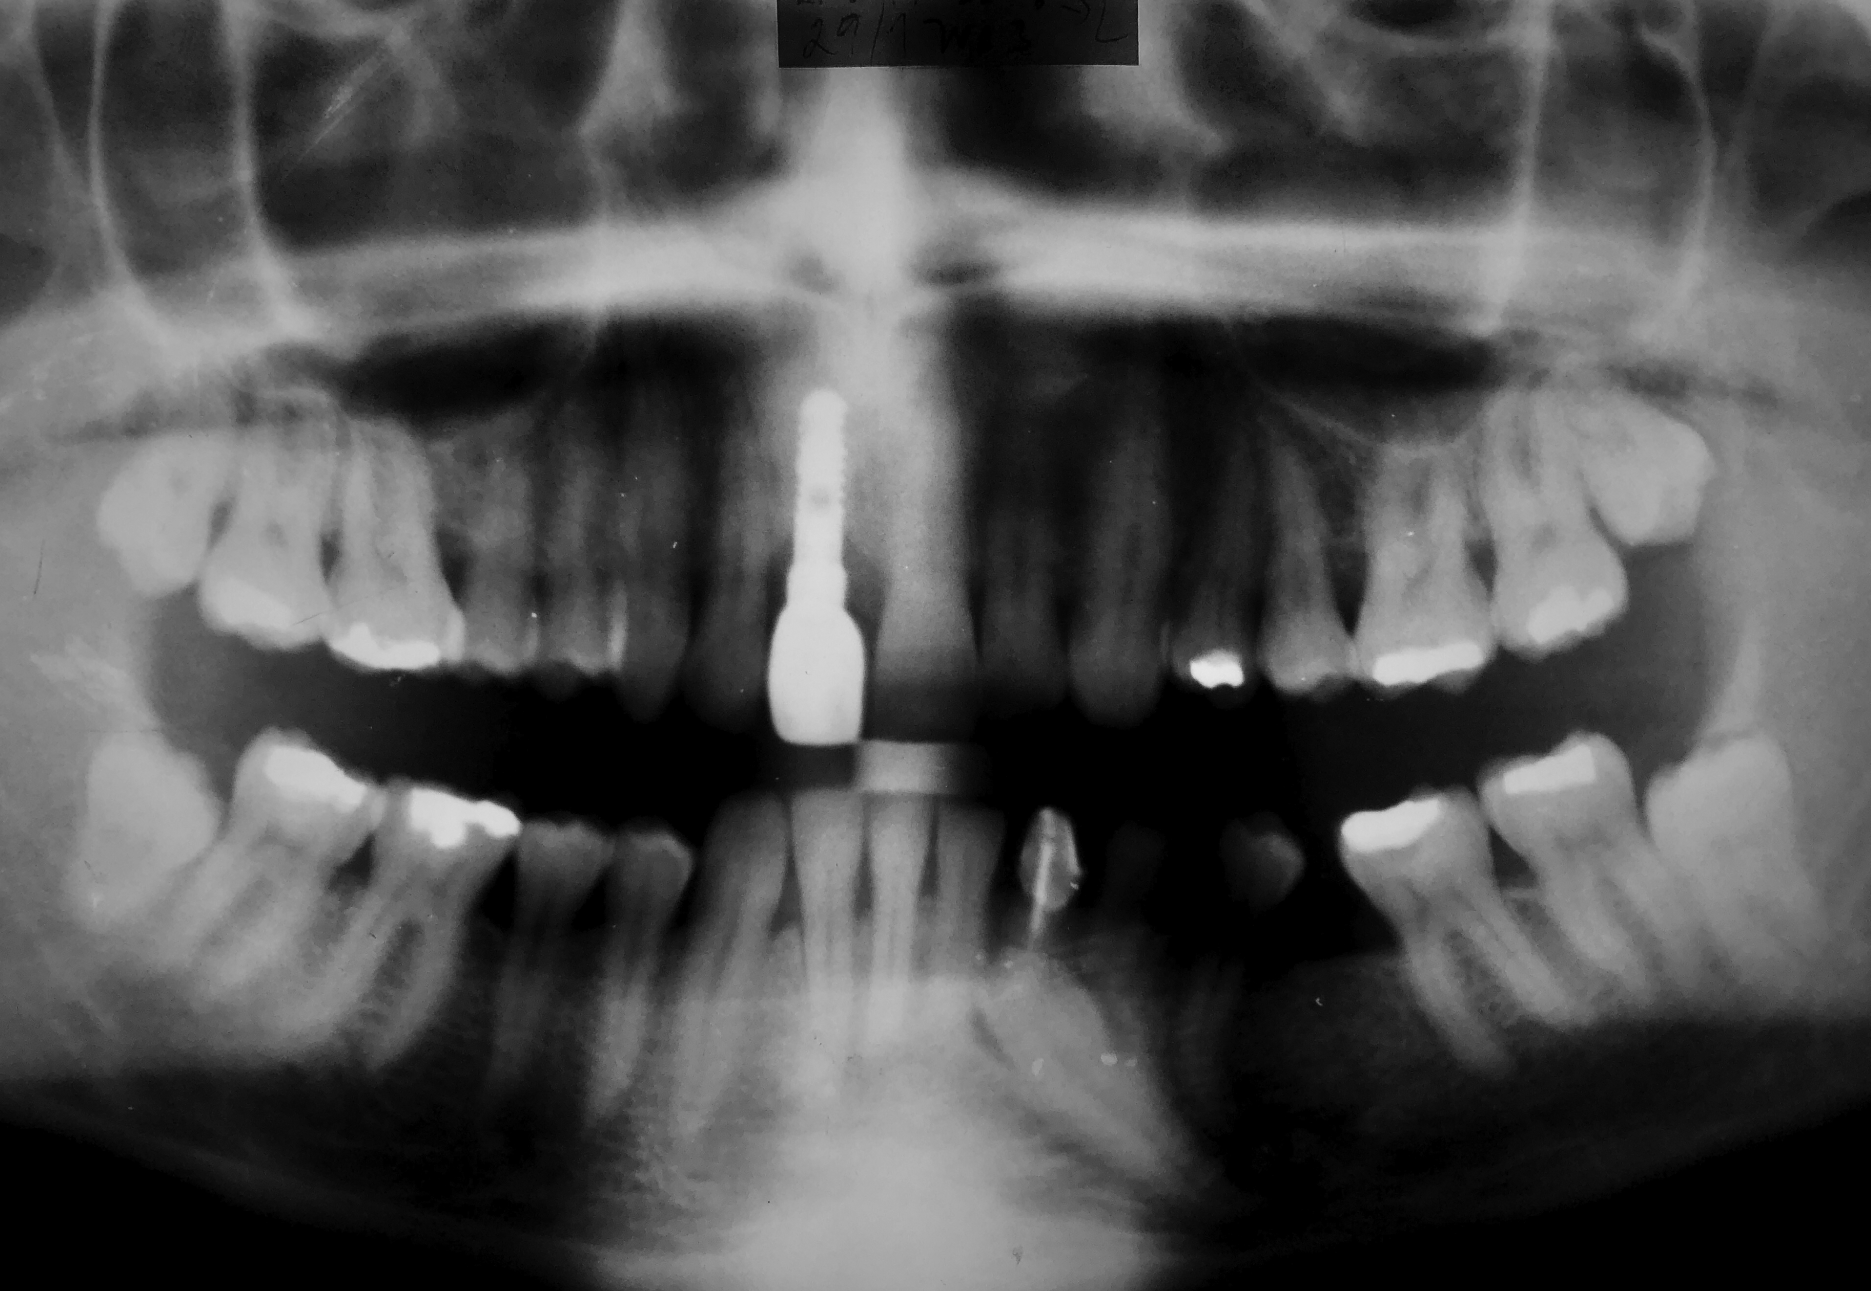

An implant with a diameter of 3.7 mm and a length of 12 mm was inserted in November 2001. A follow-up X-ray was taken 5 months after implantation.

After the implant healed, a metal-ceramic crown was fitted in June 2002. No objective or subjective changes were noted during regular recalls. Follow-up X-ray was taken in January 2003.